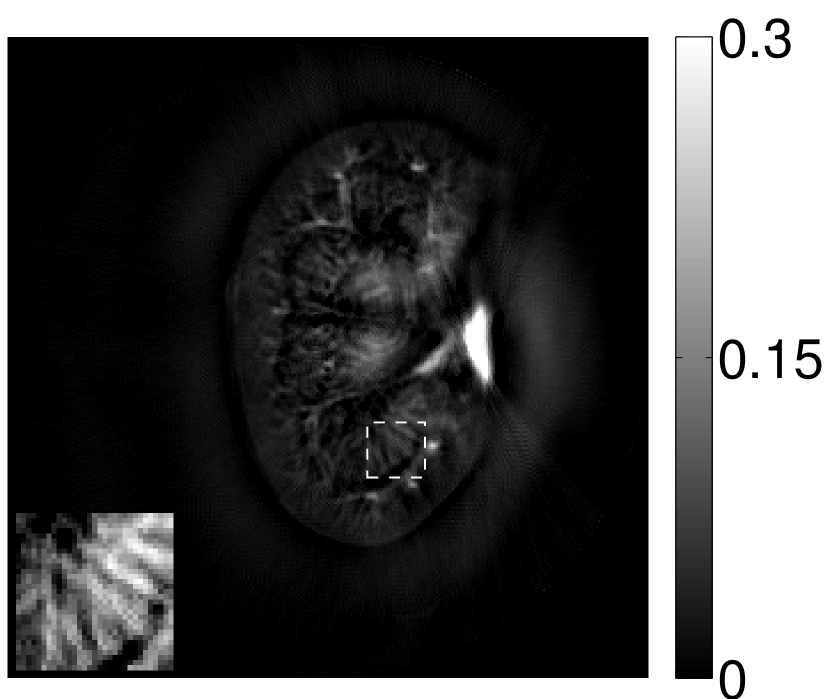

The images and EIRs reconstructed by use of the VP algorithm that was based on the 2D imaging model that neglected the SIR are shown in Figures 15 and 16. The latter figure contains results corresponding to different values for the regularization parameter . From Fig. 15, it can be observed that use of the conventional iterative method that utilized the measured EIR resulted in distortions and loss of details in the reconstructed images. Use of the VP algorithm improved the contrast and the details in the reconstructed images (Fig. 15(c) and 16(a)). Furthermore, the images reconstructed by use of the VP algorithm had a more uniform background.

In Figure 17, the results corresponding to use of the 3D imaging model that incorporated SIR effects are shown. The EIR estimated by the VP algorithm is also shown. In Figure 18, images and EIRs reconstructed by use of the VP algorithm with different regularization parameters values are shown.

Similar to the case described above where the transducer SIR was neglected, these results reveal that use of the VP algorithm can produce images with a cleaner background and enhanced spatial resolution than yielded by use of a conventional iterative algorithm that employed the measured EIR. For example, detailed information regarding the vessels near the organ’s periphery was better preserved by the VP algorithm than by the conventional iterative algorithm. These images corroborate our assertion that the VP algorithm can significantly reduce the artifacts and distortions in the reconstructed image. It is also worth pointing out that, unlike the numerical phantom studies, the artifacts and distortions in the images may be caused not only by the inaccurate EIR but also by other factors, such as neglecting acoustic heterogeneities and the variation of the EIRs among the elements of the transducer array. In such cases, the EIR estimated by the VP algorithm represents an effective system impulse response that minimizes the inconsistency between the measured data and the imaging model.